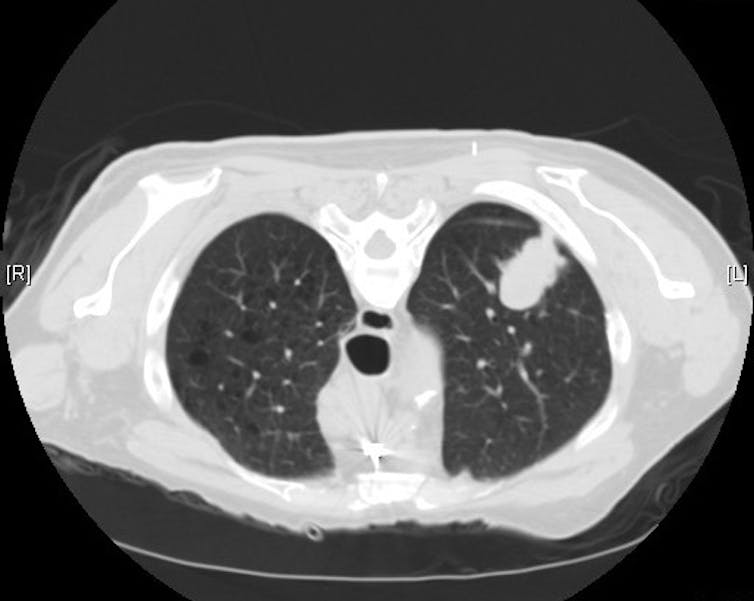

In 2021, the United States Preventive Services Task Force updated its lung cancer screening guidelines to include younger patients with less smoking history. Now, lung cancer screening is recommended for adults ages 50 to 80 who have smoked at least one pack per day for 20 years, current smokers and former smokers who quit smoking within the last 15 years. Women at risk for lung cancer can talk to their doctors about ordering a low-dose CT scan for lung cancer screening.